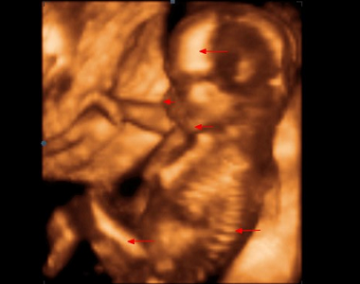

Obrázky z ultrazvuku (17.-20. týden od oplození / 19.-22. týden těhotenství)

Sonogram 4: Plod v 19. týdnu vývoje (21. týden těhotenství). Pohled z boku dokumentuje vyrovnávání disproporcí mezi mozkovou a obličejovou částí hlavičky. Nejdelší šipka označuje čelo, před ní krátká nosní kůstku a spodní šipka ukazuje na horní čelist. Tento týden je vhodný k provádění II. ultrazvukového screeningu. V oblasti zad se ostře rýsují jednotlivé obratle.